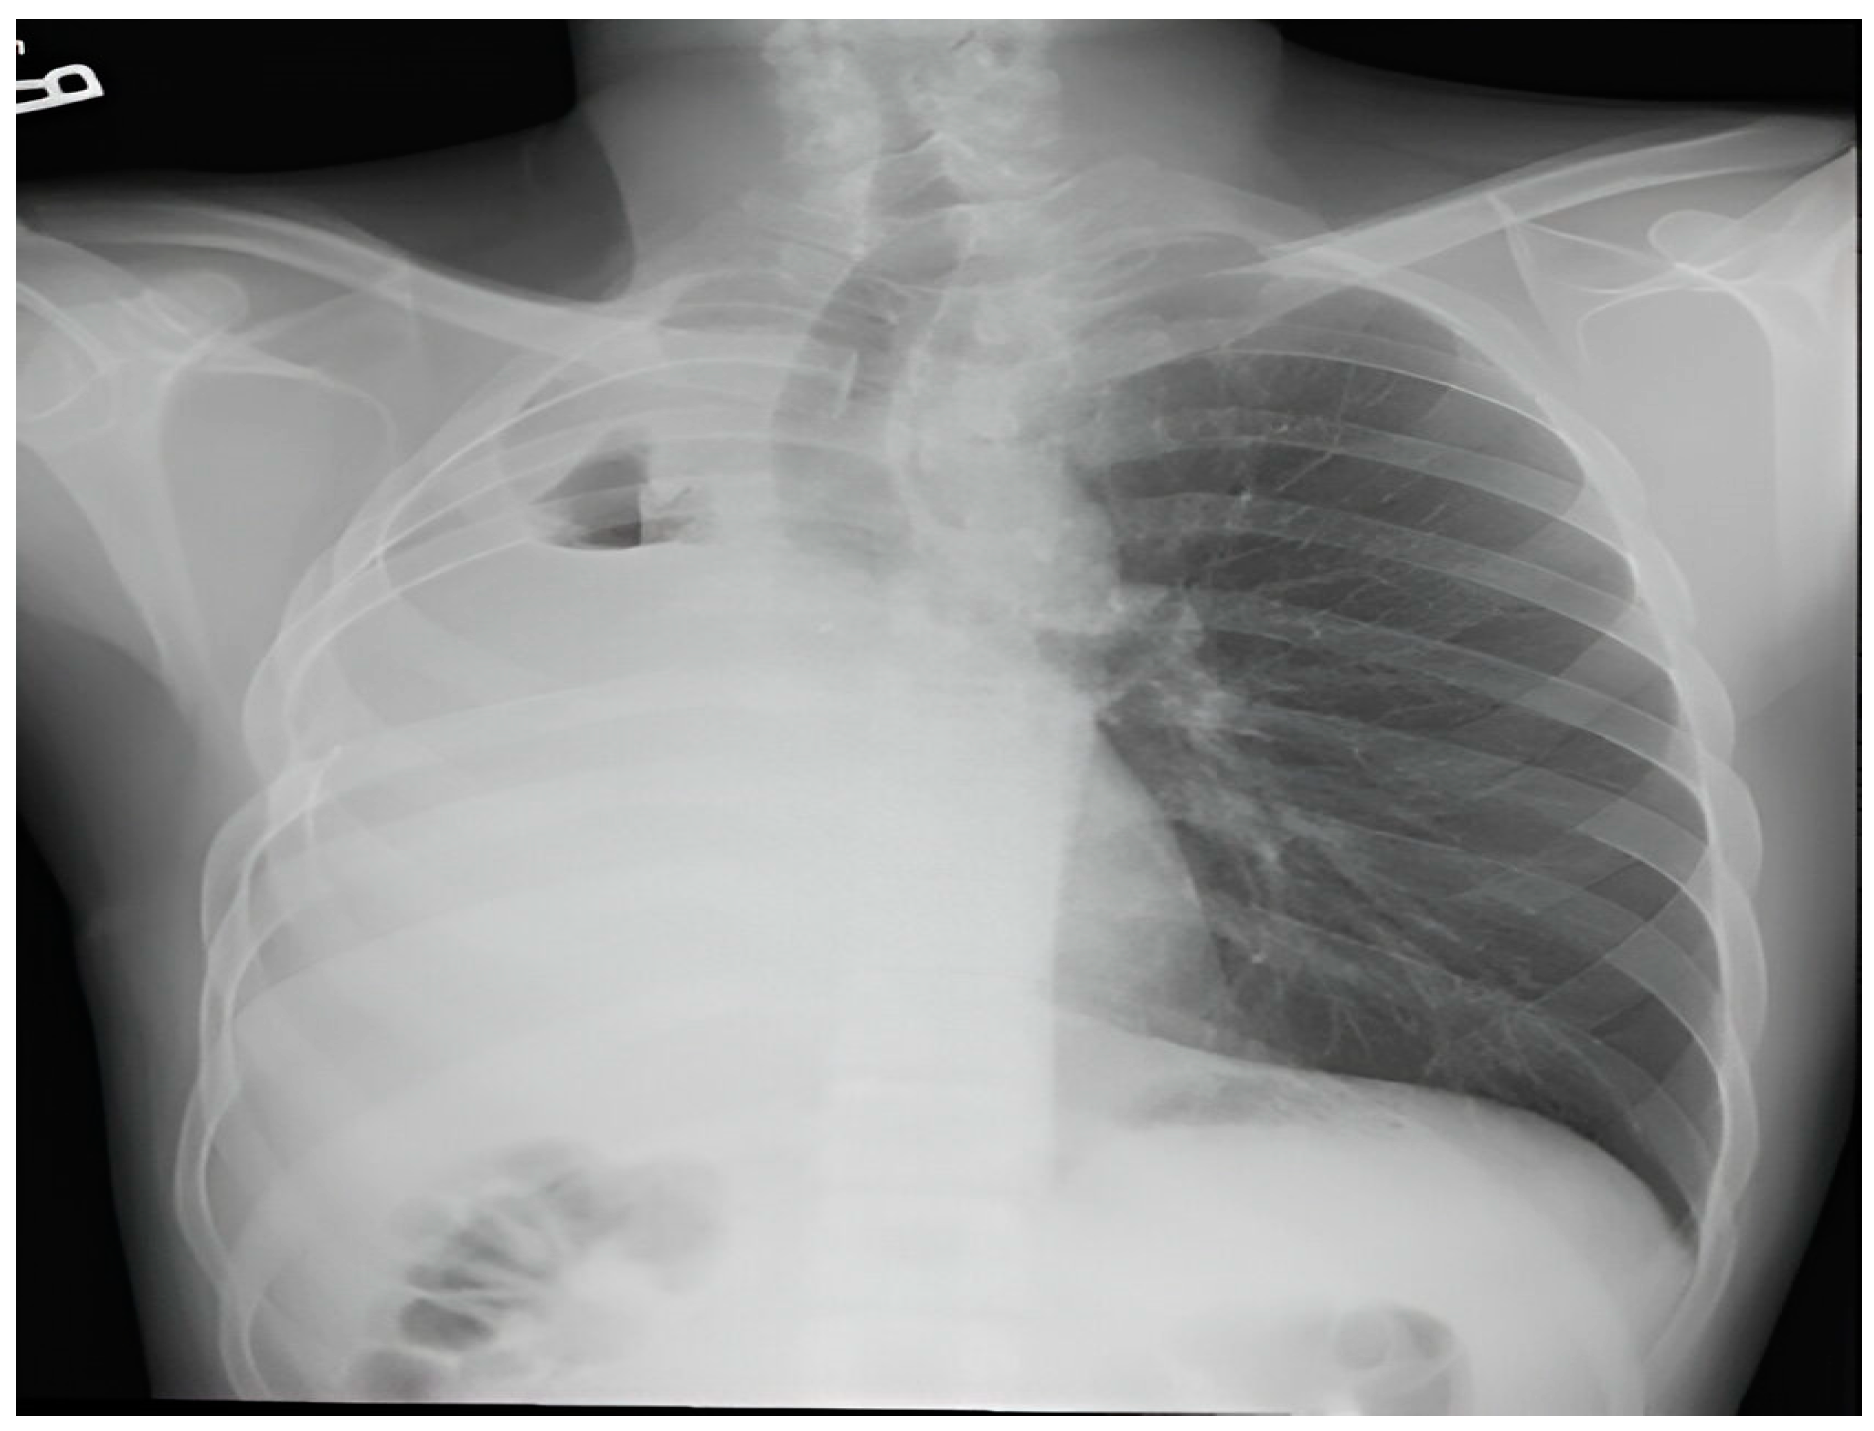

Upon evaluation at our institution, a chest radiograph displayed a sizable homogenous opacity in the right inferior mediastinum, prompting the ordering of a PET scan. The PET scan unveiled a hypermetabolic lesion located in the right main bronchus, as illustrated in Figure 1. Subsequent examination via flexible bronchoscopy exposed a fistula in the right bronchus intermedius and an elongated bronchial stump on the right side extending towards the secondary carina. Despite these findings, the patient's general clinical examination was unremarkable.

Radiologically, IMTs present with variable and nonspecific features depending on their location [14]. On CT, Pulmonary IMTs show heterogeneous enhancement and may be associated with atelectasis and/or pleural effusions. Amorphous or dystrophic calcifications in pulmonary IMTs are frequently present, usually in children more than adults [15, 16]. MRI can reveal heterogeneous signal intensities, and FDG-PET scan demonstrates high uptake [14]. In this case, there was intense FDG uptake noted in a circular pattern beneath the right main bronchus.

Figure 1. PET scan shows a hypermetabolic lesion around the right bronchial stump.